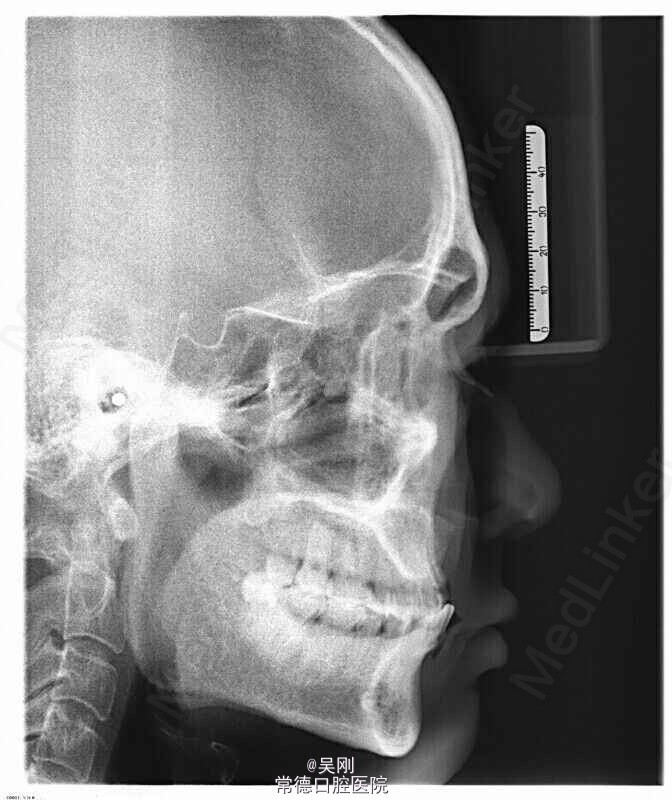

11、12、21缺失,牙槽骨(唇侧更明显)吸收严重成月牙状。 22残根断面距龈上约1.5mm,13牙髓坏死。 深覆 牙合 。 下前牙之间有间隙。 缺牙区距离太长,超过实际距离。 X线显示下前牙与上颌缺牙区牙槽嵴角度成反 牙合 。

上颌牙列缺损。 1.戴 牙合 垫,暂时恢复美观并为粘固下颌托槽开辟间隙。为防止 牙合 垫压低后牙而影响定位咬合关系,牙合 垫在前磨牙处不接触,距离抬高到能粘固托槽就好,尽量缩短佩戴时间。 2.将托槽按同一平面粘固,前牙减径约1mm(加上本身的间隙共产生约2.5mm),直接用圆丝(硬丝)挂一类牵引,使前牙牙轴具有舌向关闭间隙。 3.基牙预备,因缺牙区跨度超过实际长度选择增加14做基牙。 4.完成烤瓷桥。 5.X线显示磨牙还是有点牙低,下前牙明显内收,于上颌牙槽嵴关系改善。 6.因磨牙压低,下前牙舌侧固定保持。磨牙自己建 牙合 。